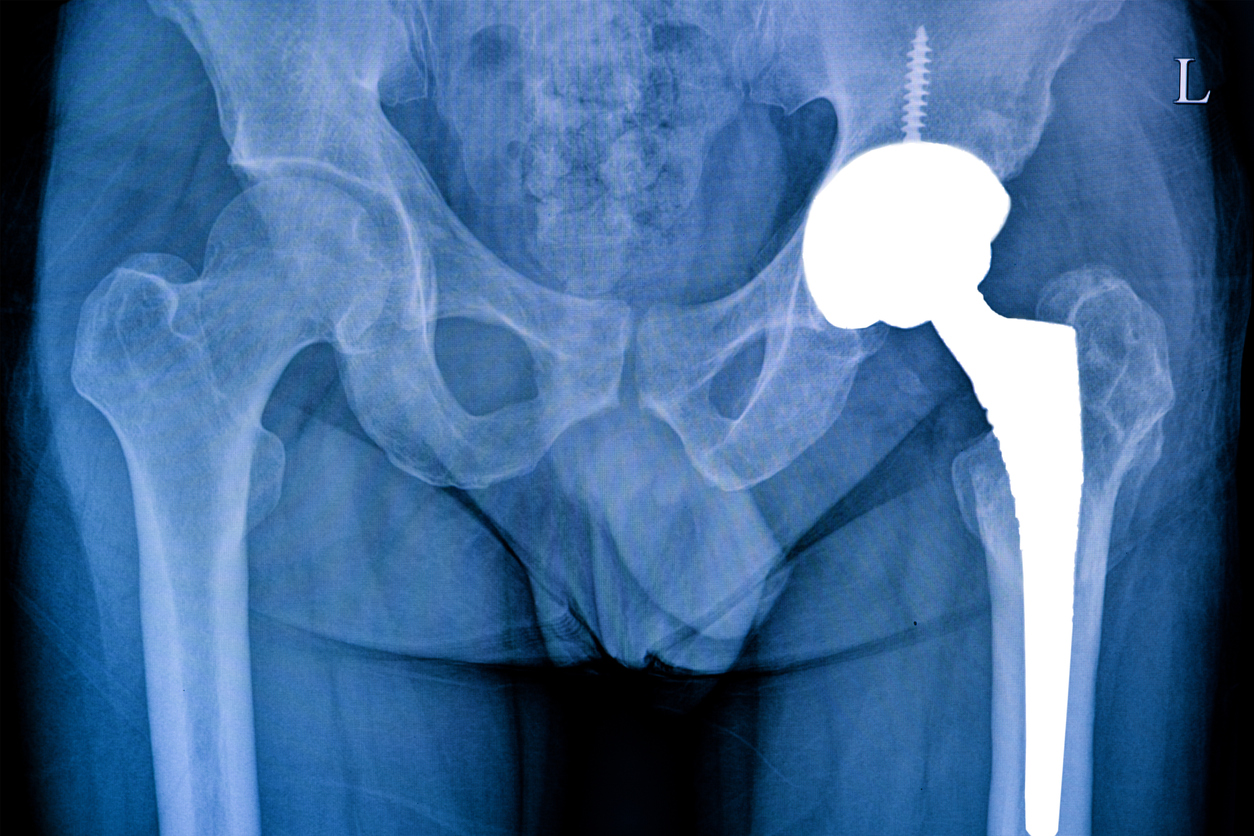

Cobalt chrome has high wear resistance and the surface can be electropolished to a smooth surface to prevent contamination. It is used for joint replacements, hip and shoulder socket replacements, and dental implants.

Stainless steel is also used for orthopedic products such as hip and knee replacement joints, and in screws and plates used to stabilize broken bones. Stainless steel mesh is often used for intravascular stents.

Corrosion-resistant titanium is found in many types of medical appliances and is now a common substitute for stainless steel to make lightweight, yet durable skeletal supports and bone replacements. Titanium is also used in dental implants; it can be metal 3D printed to create customized parts from a patient’s scans and X-rays.